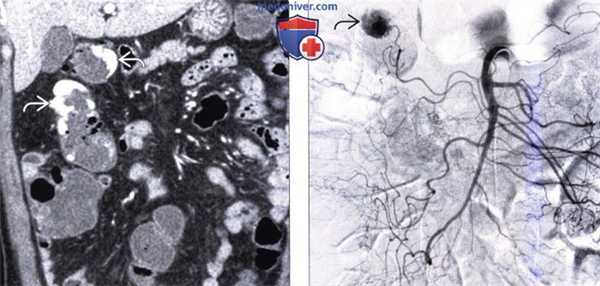

(a-б) На поперечных КТ-срезах сигмовидной ободочной кишки определяется сегментарное утолщение стенки и множественные дивертикулы, окруженные «мутной» жировой клетчаткой брыжейки сигмовидной кишки (длинные стрелки). Утолщенная стенка ободочной кишки имеет слоистый характер контрастного усиления.

(в) Воспаленный дивертикул (стрелки на б, в) перфорирован, и газ из просвета кишки попал в брыжейку сигмовидной кишки. Воспалительный процесс распространился на расположенный рядом жировой привесок, приведя к развитию вторичного эпиплоического аппендагита (короткая стрелка).

(г) На поперечном КТ-срезе на уровне проксимальных отделов восходящей ободочной кишки у другого пациента визуализируется воспаленный дивертикул с утолщенной, накапливающей контраст стенкой (указатель).

(д) На поперечном КТ-срезе, выполненном на 5 мм в краниальную сторону (выше) по сравнению со срезом (г) определяется помутнение жировой клетчатки воспалительного характера, более выраженное вблизи причинного дивертикула, чем в прилежащих отделах брыжейки ободочной кишки (длинная белая стрелка). Стенка ободочной кишки утолщена, имеет слоистый характер контрастного усиления (длинные черные стрелки на г, д). Линейное скопление жидкости визуализируется в основании брыжейки ободочной кишки (короткие белые стрелки на г, д).